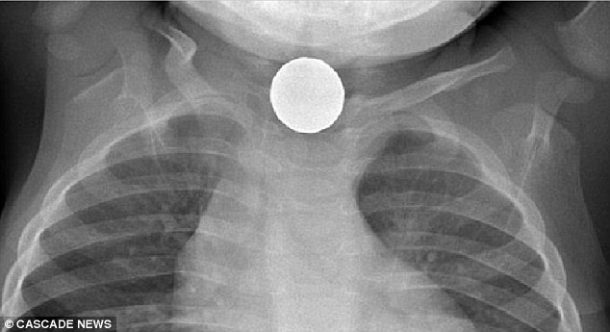

图片来源:级联新闻

“如果电池被卡在上方食道上,并且假设电池进入时电池是'Live',则您可以在大约15分钟内开始看到食道衬里的损坏。我们已经在四个小时内看到了食道破裂。如果它侵蚀了食道并进入气道,则它会在食道和气道之间创建一个开口感染。”